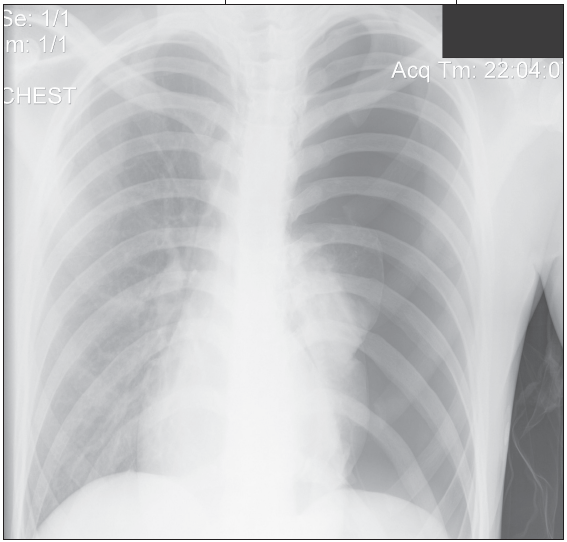

In the ED, the patient's temperature was 37.8°C (100°F); heart rate was 100 beats per minute; respiratory rate, 28 breaths per minute; and blood pressure, 124/96 mm Hg. Oxygen saturation was 100% on room air. He had no nasal flaring but used accessory respiratory muscles. The trachea was in midline. Breath sounds were markedly diminished on the left side, with good air entry on the right. No crepitus, wheezing, stridor, or crackles were appreciated. Cardiac examination revealed a normal S1 and S2, without any murmurs, rubs, or gallops. Mediastinal shift could not be detected clinically. Chest films showed a left-sided tension pneumothorax (Figure 1).

A chest tube was placed, and symptoms resolved (Figure 2). The patient underwent surgery to resect an apical pleural bleb.